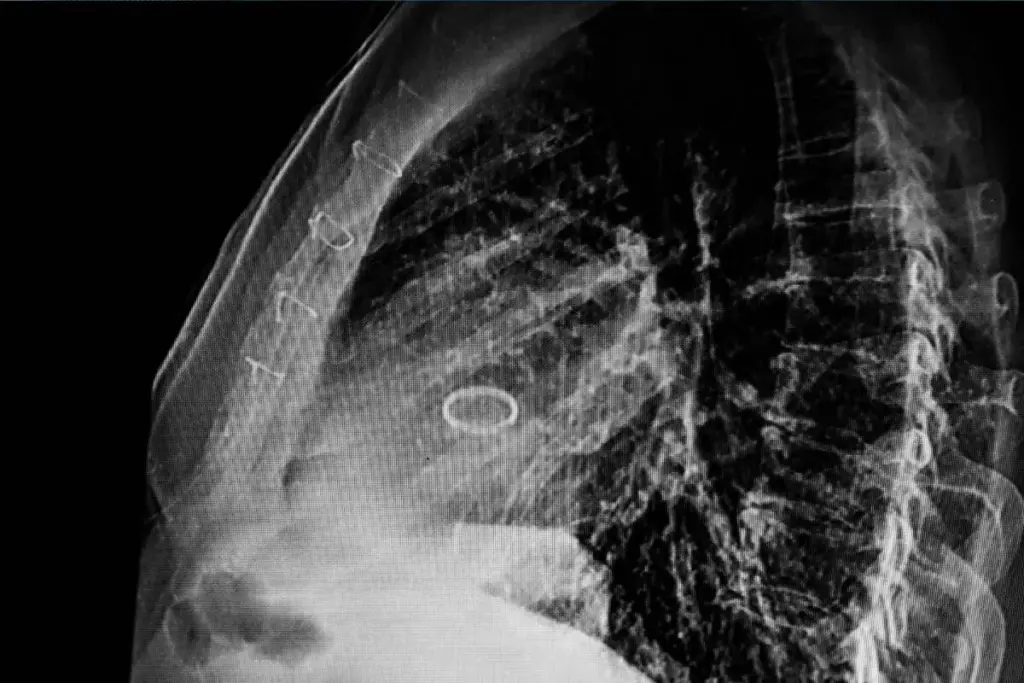

Advanced Imaging Techniques for Valve Assessment

Advanced imaging is vital for spotting severe valve problems. Echocardiography gives clear views of how valves work. It spots issues like advanced stenosis and valve wear.

Cardiac MRI also helps, showing the heart and valves in high detail. It’s a big help in diagnosing problems.

- Echocardiography for valve structure and function assessment

- Cardiac MRI for detailed heart and valve imaging

- CT scans for assessing valve calcification and surrounding structures

Impact of Valve Calcification on Survival

Valve calcification greatly affects survival in valve disease patients. It can cause stenosis or regurgitation, making treatment harder and sometimes needing surgery.

Studies link valve calcification to a higher death risk. This shows why it’s vital to watch and manage calcification in valve disease patients.